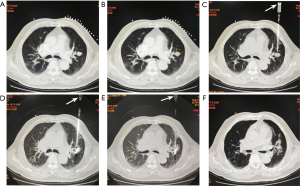

The procedures of group B

The preoperative preparation and PN localization procedures were identical to those in group A. The difference is that in group B, PB was performed first, followed by MMA immediately. The steps of tissue specimen extraction, specimen processing, ablation power, ablation time, and ablation range were the same as those in group A. The operation flow of the representative case of group B is shown in Figure 3.